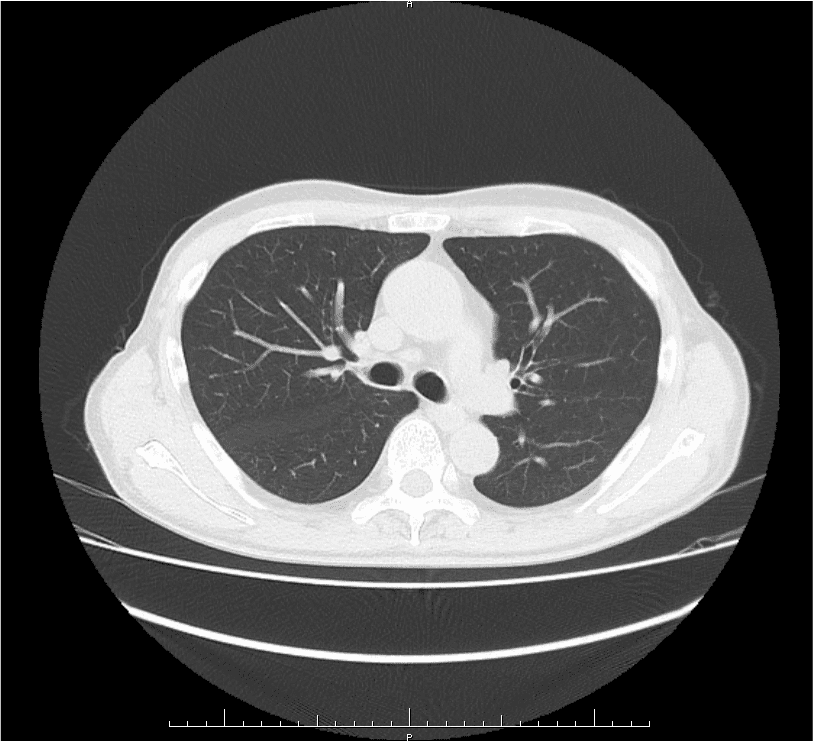

胸腹部CT + 体幹部筋肉・脂肪測定

胸腹部CTで肺や腹部臓器の病気、フレイルの早期発見をサポート

胸腹部CT検査では、肺や腹部臓器を高精度にチェックできます。早期の肺疾患や消化器系の病気(肝臓、膵臓、胆嚢、腎臓など)を発見することができ、早期治療のきっかけになります。

胸腹部CTのメリット

- 肺疾患の早期発見:

肺癌や慢性閉塞性肺疾患(COPD)、肺気腫など、早期の段階では自覚症状が少ない病気を発見できます。 - 主要な血管の異常をチェック:

血管の石灰化の有無を観察することで、脳血管疾患や心疾患などのリスクを事前に察知することが可能です。 - 腹部臓器の異常を検出:

肝臓、膵臓、胆嚢、腎臓などの病気(腫瘍や炎症など)を見つけ出すことができます。 - 非侵襲的で簡単:

痛みや負担が少ない検査で、短時間で体内の詳細な画像が得られます。